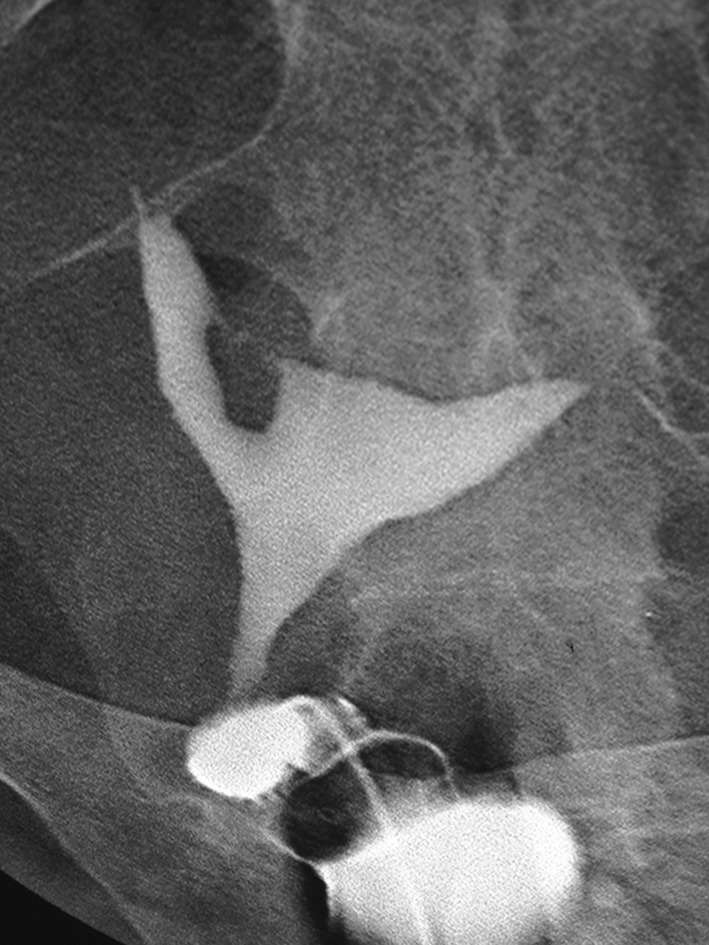

چسبندگی داخل رحمی یکی از علل شناخته شده ناباروری است. HSG و 2D SIS دو روش رایج برای تشخیص آن هستند، در حالی که هیسترئوسکوپی استاندارد طلایی است. نقش 3D USG در تشخیص به طور گسترده مورد بررسی قرار نگرفته است. یک مطالعه با مقایسه 3D USG و HSG گزارش داد که 3D USG دارای حساسیت 100٪ و HSG 66.7٪ برای تشخیص صحیح و درجه بندی چسبندگی های داخل رحمی است. HSG عمدتاً در تشخیص چسبندگی بخش تحتانی رحم شکست خورد و آنها را با انسداد کامل حفره اشتباه گرفت . احمدی تصدیق کرد که SIS سه بعدی ابزاری مفید و کم تهاجمی است.

هیستروسالپنگوگرافی سینکیا داخل رحمی